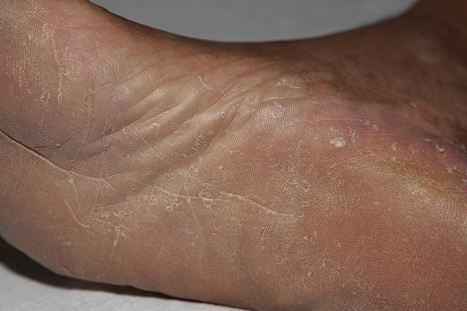

Chronic Hyperkeratotic Type.

Usually bilateral with patchy or diffuse scaling limited to the thick skin, soles, and the lateral and medial aspects of the feet, this is also known as “moccasin-type” tinea pedis. T. rubrum, the most common etiology, produces very few minute vesicles, leaving collarettes of scale less than 2 mm in diameter. Erythema is variable.